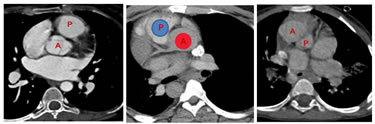

Figure 1:

DISCUSSION With the advancement of diagnostic radiology there is undoubted positive impact on the patient management. Imaging modalities play a key role when it comes to planning the treatment /surgery. Cardiac MRI is another promising technology which allows dynamic evaluation of the heart. The time consumption of scan and the requirement of general anesthesia makes the clinician to go for CT over MRI in most cases of CHDs .The increased slice thickness and the respiratory artifacts adds the limitation of MRI in the morphological evaluation of CHD. Computed tomography (CT) has an important role in the morphological evaluation of patients with congenital heart disease (CHD). We can obtain isotropic volume data, and high-quality two- and three-dimensional multiplanar reformatted images. A systematic approach to the cardiac imaging will simplify the complexity in diagnosis without compromising the quality of reporting. The approach should start with describing the Van Praagh notation of our study cases. It is helpful for structuring the interpretation of imaging studies as well as the reporting of results. It includes Viscero atrial Situs, Ventricular Loop Orientation and Position and Relation of the Great Vessels. In normal anatomic configuration’{S, D, S}’, the first ’S' indicates that the morphologic right atrium and largest hepatic lobe are on the patient’s right and the morphologic left atrium, stomach, and spleen are on the left side (ie; situs solitus). D indicates that the ventricular loop is curved rightward (dextro- or d-loop). The last ‘S' indicates that the aorta is posterior to and rightward of the main pulmonary artery (situs solitus). The abnormality in viscero atrial situs are situs inversus and situs ambiguous. In situs inversus right atrium and largest lobe of the liver are on the left side of the patient and the morphologic left atrium, stomach, and spleen are on the right, assign the letter I for situs inversus. If the visceroatrial arrangement does not fit into either of these categories, assign the letter A to represent situs ambiguous. For determining the ventricular loop orientation, first try to identify the morphologic right and left ventricles on the basis of their intrinsic characteristics . If the morphologic right ventricle is located rightward of the morphologic left ventricle it is dextro loop (D loop). If reverse , it is levo loop (Lateral-loop). The third step is to determine the position and relation of the great vessels. In the normal configuration of the great vessels, the aorta is posterior to and rightward of the main pulmonary artery (MPA). It is designated by the letter S to denote situs solitus, “{_, _, S}” . When the aorta maintains its normal posterior relation to the MPA but has an inverted position leftward of the MPA, it is called situs inversus, designated as “{_, _, I}”. If the aorta is anterior to and rightward of the MPA, the anomaly is described as dextrotransposition, or d-transposition, of the great vessels, which is denoted as “{_, _, d-TGV}”; if the aorta is anterior to and leftward of the MPA, the anomaly is described as levotransposition (l-transposition) or congenitally corrected transposition, which is denoted as “{_, _, l-TGV}.” If the aorta is neither anterior nor posterior to the MPA, the great vessels are usually described as malpositioned. In the next step we have to look for the cardiac chambers and ventriculoarterial connection, relationship between the upper lobe bronchi and pulmonary arteries,the great vessels ( aorta, pulmonary artery, pulmonary vein), coronary artery, valves, systemic veins (superior vena cava, inferior vena cava, hepatic veins). Before going into the cases, it is important to know about the developmental anatomy of heart.In early embryonic development, the heart is a linear tube consisting of several segments that eventually give rise to the main cardiac components. Proceeding caudocephalad along this tube (from the proximal to the distal end), these segments include primitive atria, the left ventricular structure, the bulbus cordis (which will develop into the right ventricle), and the truncus arteriosus (the future great vessels) .During development, the tube bends over on itself, toward either the right or the left. Normally, the cardiogenic crescent folds to the right, forming a d-loop, with resultant positioning of the bulbus cordis to the right of the left ventricle . As the loop forms, the cephalic end of the heart tube bends ventrally, caudally, and slightly rightward to establish the spatial relationships of the future heart chambers. Figure 4: SITUS SOLITUS; SITUS INVERSUS; D-TGV